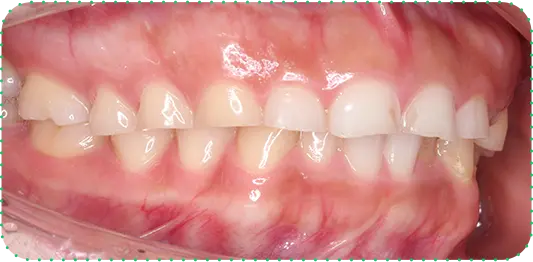

Before

After

主訴

上の前歯が長くて気になる

治療期間

9か月

治療費

30万円

治療内容

右上1番を小矯正治療にて歯茎を増やし、右上1番と左上1番をセラミッククラウンにて修復

治療のリスク

咬み合わせによっては、セラミックが欠ける可能性があります。